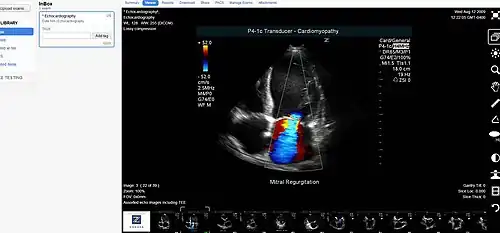

Medical image sharing is the electronic exchange of medical images between hospitals, physicians and patients. Rather than using traditional media, such as a CD or DVD, and either shipping it out or having patients carry it with them, technology now allows for the sharing of these images using the cloud. The primary format for images is DICOM (Digital Imaging and Communications in Medicine). Typically, non-image data such as reports may be attached in standard formats like PDF (Portable Document Format) during the sending process. Additionally, there are standards in the industry, such as IHE Cross Enterprise Document Sharing for Imaging (XDS-I), for managing the sharing of documents between healthcare enterprises. A typical architecture involved in setup is a locally installed server, which sits behind the firewall, allowing secure transmissions with outside facilities. In 2009, the Radiological Society of North America launched the "Image Share" project, with the goal of giving patients control of their imaging histories (reports and images) by allowing them to manage these records as they would online banking or shopping.[1]

- DICOM - A standard for handling, storing, printing, and transmitting information in medical imaging.